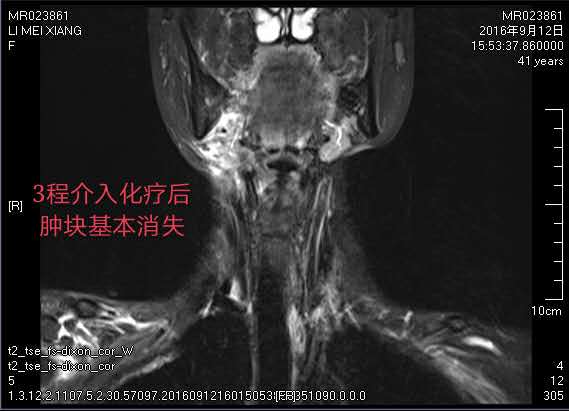

第一次介入治療后,腫瘤就縮小了一半,出血也逐漸停止,頸部潰爛的皮膚逐漸好轉(zhuǎn),為接下來的局部放療創(chuàng)造了條件。為鞏固治療,李大姐一共接受了三個療程的微創(chuàng)介入灌注治療,目前右頸部巨大腫塊已基本消退。治療后身體日漸康復(fù)的李大姐對未來充滿了信心。